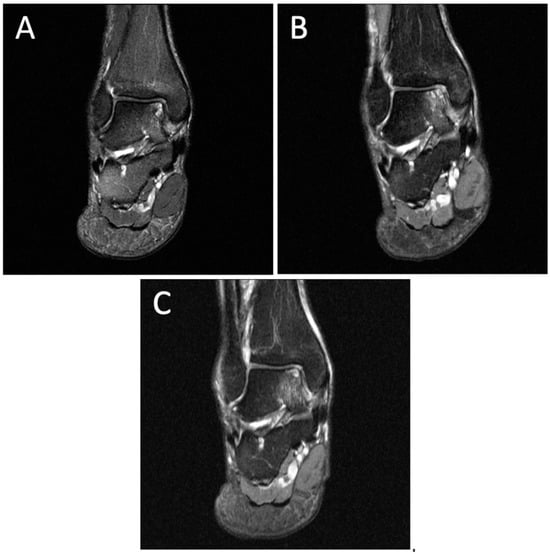

Figure 2.

Degenerative progression of the left medial osteochondral lesion outlined in red on coronal MRIs from 2009 to 2021. The timeline of lesion progression includes MRI scans from 2009 (A), 2011 (B), 2016 (C), 2017 (D), 2018 (E), 2019 (F), and 2021 (G). Over 12 years, the lesion progressed in size from 11.2 mm × 10.4 mm to 13.2 mm × 15.3 mm on this coronal MRI.